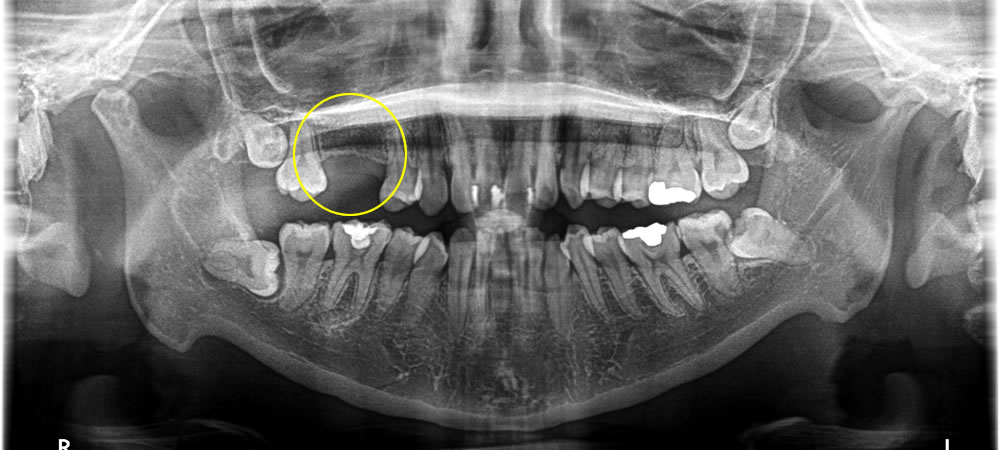

こちらの患者さまは、歯がない部分にインプラントを入れたいとのことで来院された患者さまです。他院で歯を抜いた後、期間があいていたため、すぐに日取りを決めてオペを行いました。

レントゲンでの検査の結果、抜歯後の予後が悪かったため、インプラントの持ちを良くするために骨造成を同時に行っています。